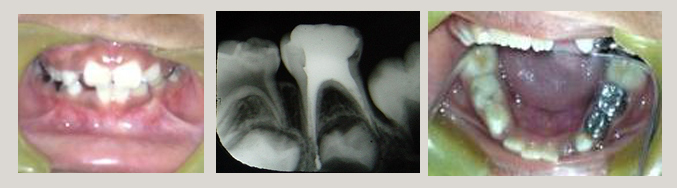

Child - Root Canal Treatment and Crown